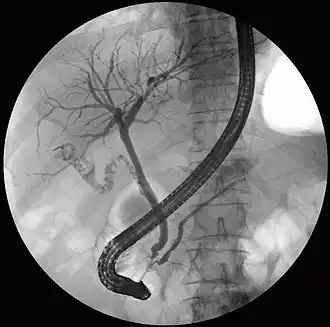

ERCP image showing the pancreatic duct and biliary tree.